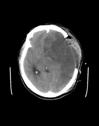

3).颅骨凹陷性骨折术前 术后

4).颅骨修补术 DR片 三维重建